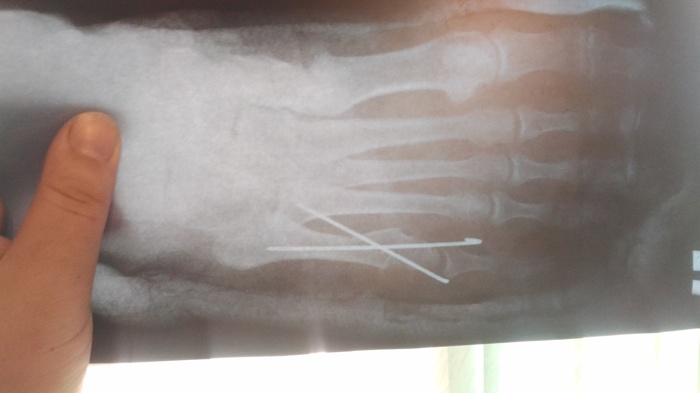

Во Вредена предложили три варианта поставить либо спицы, либо пластину либо вообще просто напросто загипсовать. Ложится в больницу брат не захотел, так как работает на дому(архитектор), а из больницы работать сложновато (возможно зря), решили поставить спицы и вот такая картинка получилась

Отсидев в очереди два часа (что еще не так много на самом деле), мы зашли в кабинет к врачу, не дав и слова сказать он начал на повышенных тонах отчитывать брата рассуждая, а стоит ли вобще брать его на прием. Никаких оправданий он выслушивать не захотел, говорил все время на повышенных тонах брат вышел из кабинета, так как он разозлился от такого обращения и сказал, что вобще ни к какому врачу не пойдет. Пока суть да дело, я договорилась что нас примет дежурный врач. На приеме выяснилось, что у брата произошло смещение отломка

Вот собственно вчера были на консультации, доктор увидев снимки спросил кто сотворил сей ужас (про спицы). Сказал, что при таких переломах спицы на закрытую не ставят, нужно обязательно делать операцию, ставить либо пластинку либо шуруп, в зависимости от обстоятельств. А так одна спица немного кость держит, а другая вобще ничего не фиксирует. Операция платная и дорогая соответственно, за деньги мы к сожалению не можем себе ее позволить. У подруги (она врач) узнавала - бесплатно можно сделать, но тут 50 на 50, как она сказала скорее всего соберут плохо. Можно по направлению делать во Вредена и оплатить палату, что бы не так долго очередь ждать. Можно вообще ничего не делать, но тогда сказали что возможно будут проблемы при ходьбе, так как кость опорная, а в последствии могут быть проблемы с позвоночником.